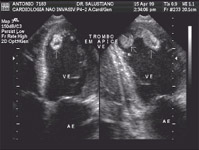

Através da ecocardiografia com Doppler é possível então fazer uma avaliação completa das doenças que comprometem o coração. Portanto, nas valvopatias é possível quantificar com exatidão o grau de estenose ou insuficiência. Nas miocardiopatias pode-se estabelecer o grau de disfunção miocárdica através do cálculo das dimensões cardíacas e da fração de ejeção (FE). Nas cardiopatias isquêmicas a ecocardiografia, além de visibilizar o segmento (parede) hipocontrátil, pode quantificar o grau de hipocinesia e até fazer correlação com artéria coronária envolvida.

Enfim, nas demais patologias (hipertrofia miocárdica, pericardiopatias, cardiopatas congênitas e etc) a ecocardiografia oferece ao clínico uma gama enorme de parâmetros que certamente auxiliará no tratamento desses pacientes.